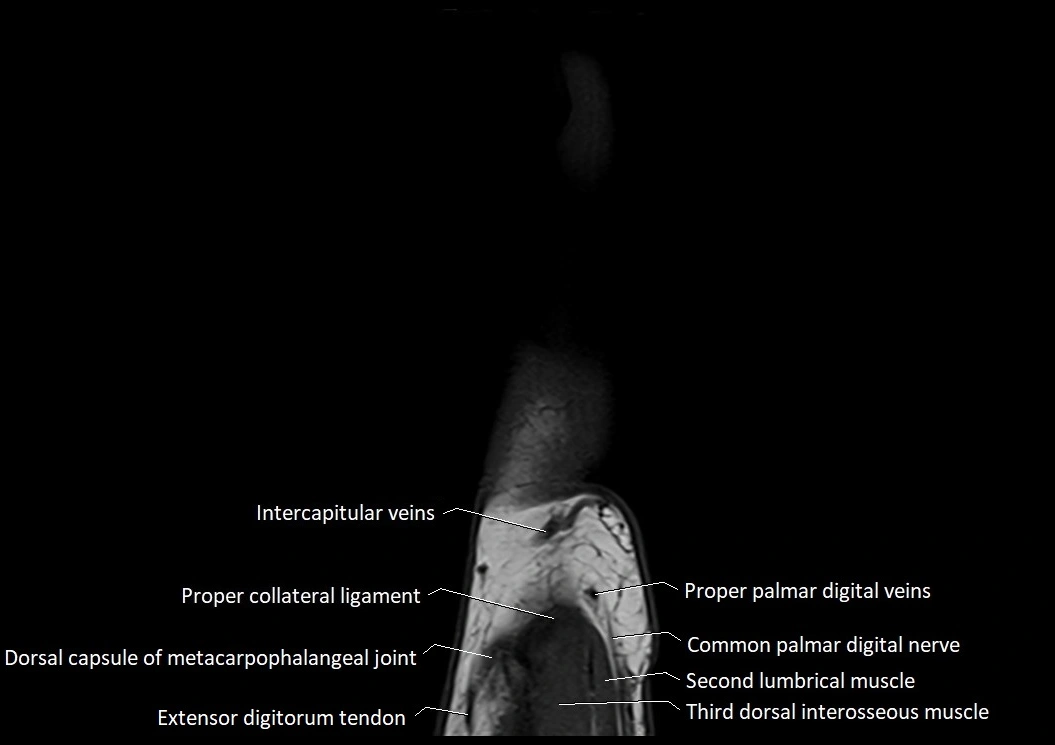

MRI images

image